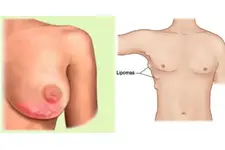

Omuzda yağ bezesi, tıpta lipom olarak adlandırılan, genellikle zararsız ve yavaş büyüyen yağ dokusu kütleleridir. Bu bezeler, vücudun herhangi bir yerinde, özellikle de omuz ve sırt bölgelerinde, ortaya çıkabilir. Genellikle yumuşak, hareketli ve ağrısızdırlar. Ancak, bazı durumlarda, bu bezelerin belirtileri ve tedavi yöntemleri hakkında bilgi sahibi olmak önemlidir. Yağ Bezesi Nedir?Yağ bezeleri, yağ hücrelerinin anormal bir şekilde birikmesi sonucu oluşan şişliklerdir. Bu kütleler genellikle derinin altında, kasların üzerinde veya iç organların çevresinde gelişebilir. Lipomlar genellikle iyi huyludur ve kanser riski taşımazlar. Belirtileri Omuzda yağ bezesi belirtileri şunlar olabilir:

Tedavi Yöntemleri Çoğu durumda, omuzda yağ bezesi tedavi gerektirmez; çünkü bu kütleler genellikle zararsızdır. Ancak, estetik kaygılar veya rahatsızlık hissi durumunda tedavi seçenekleri mevcuttur: